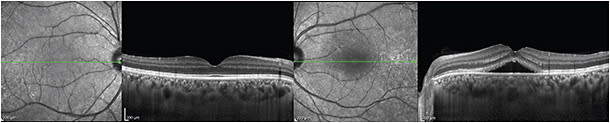

The choroid is thicker in CSR (Figure 1) than in normal eyes (414-478 µm vs 248 µm, respectively), and the choroidal vascular lumens appear enlarged.11 In chronic CSR, a “double layer sign” may appear, with an undulating RPE layer, hyporeflective middle layer, and intact Bruch’s membrane.11

Figure 1. Central serous retinopathy. A healthy 28-year-old man complained of metamorphopsia for five days after undergoing a tooth extraction. On examination, he had BCVA of 20/20 OD and 20/40 OS and an elevated macula on dilated fundus examination. EDI-OCT exhibited prominent subretinal fluid and thickened choroids in both the affected and unaffected eyes.

CREDIT: ALL IMAGES, PATRICIA GARCIA, MD

The unaffected fellow eye may also be thickened. With indocyanine green angiography, up to 65% of patients demonstrate hyperpermeability in the contralateral eye, which may account for the 20-30% incidence of bilateral disease in longitudinal observational studies.11,12

After spontaneous resolution of CSR, the choroidal thickness decreases but does not return to normal. Photodynamic therapy causes a greater change than spontaneous resolution; studies have shown initial swelling of approximately 58 µm, followed by a reduction to normal thickness. Laser photocoagulation did not significantly affect choroidal thickness.12,13